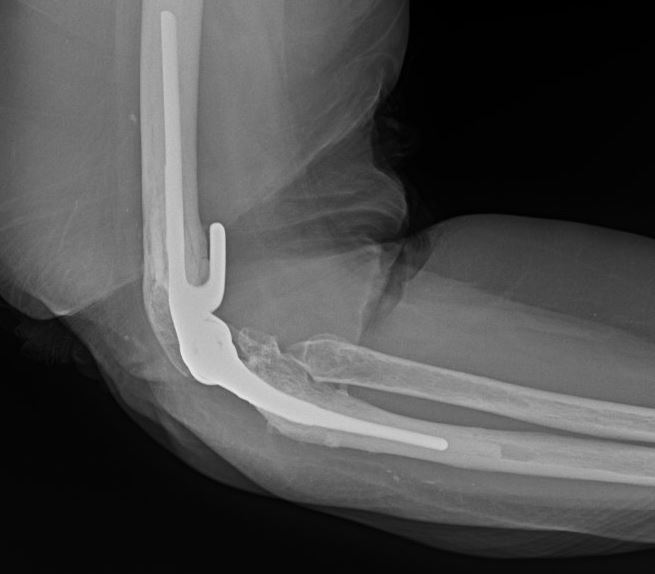

A 69-year-old male presents to the clinic for evaluation of right elbow pain with decreased range of motion. Fifteen months ago, the patient sustained a right elbow injury following a fall down the stairs and was treated with open reduction and internal fixation at an outside institution. Today, he reports continued pain and a gradual decrease in range of motion. On examination, significant crepitus is noted throughout elbow range of motion, with an arc of motion limited from 45 to 90 degrees. Pronation is limited to 40 degrees, while supination is limited to 30 degrees. Radiographs are obtained, as depicted in Figures A and B. Which of the following is true regarding the most appropriate treatment for this injury?

Figures A and B represent orthogonal views of a right elbow demonstrating post-traumatic osteoarthritis with heterotopic bone formation following olecranon ORIF and radial head replacement.